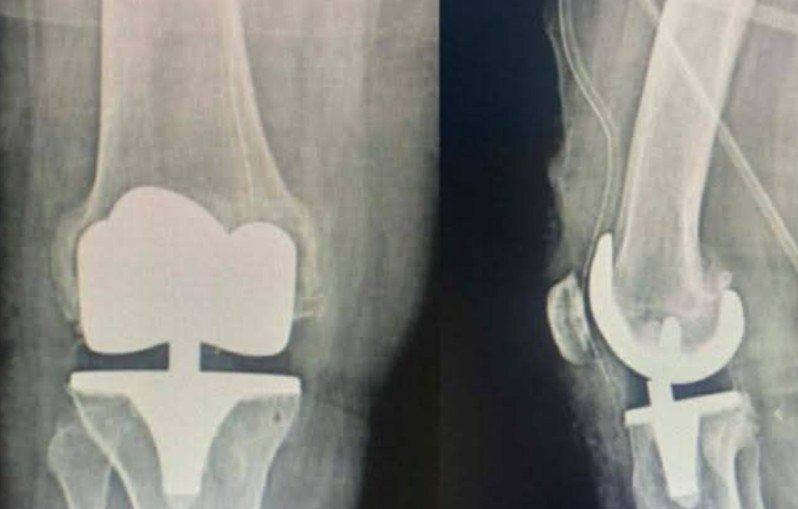

تمكّن فريق جراحة العظام بالمستشفى الجهوي جندوبة من إجراء عملية تركيب مفصل اصطناعي كامل للركبة لمريض يعاني من داء مفصل الركبة المتقدم، تحت إشراف الدكتور سيف الدين محجوبي.

وأوضحت الإدارة الجهوية للصحة أن العملية تُعد من التدخلات الدقيقة في جراحة العظام، وتمّت بتنسيق كامل مع قسم التخدير والإنعاش، وقد تكلّلت بالنجاح. ويُعتبر هذا الإنجاز خطوة مهمّة تعيد هذا النوع من التدخلات الجراحية إلى المستشفى بعد سنوات.